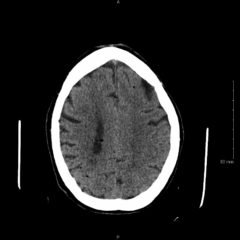

Patient’s tongue had a black discoloration, without elongated filiform papillae. We could not appreciatelymphadenopathy.His abdomen was tender to palpation. WBC of 2.2 x 103/mm3 and Hg of 11.6 g/dL, platelets of 126 x 103/mm3 (all stable from baseline). Urinalysis was amber color without blood.

Our patient’s physical finding of a tongue with black discoloration may trigger concern for potential bleeding disorder, either locally in the oral mucosa versus gastrointestinal bleed. However, the history, physical exam, and workup did not result in any evidence of bleeding. His history of increased antacid use in the setting of leukopenia suggests the cause. Understanding the differential diagnosis can help facilitate a more basic workup and simple discharge with outpatient management.